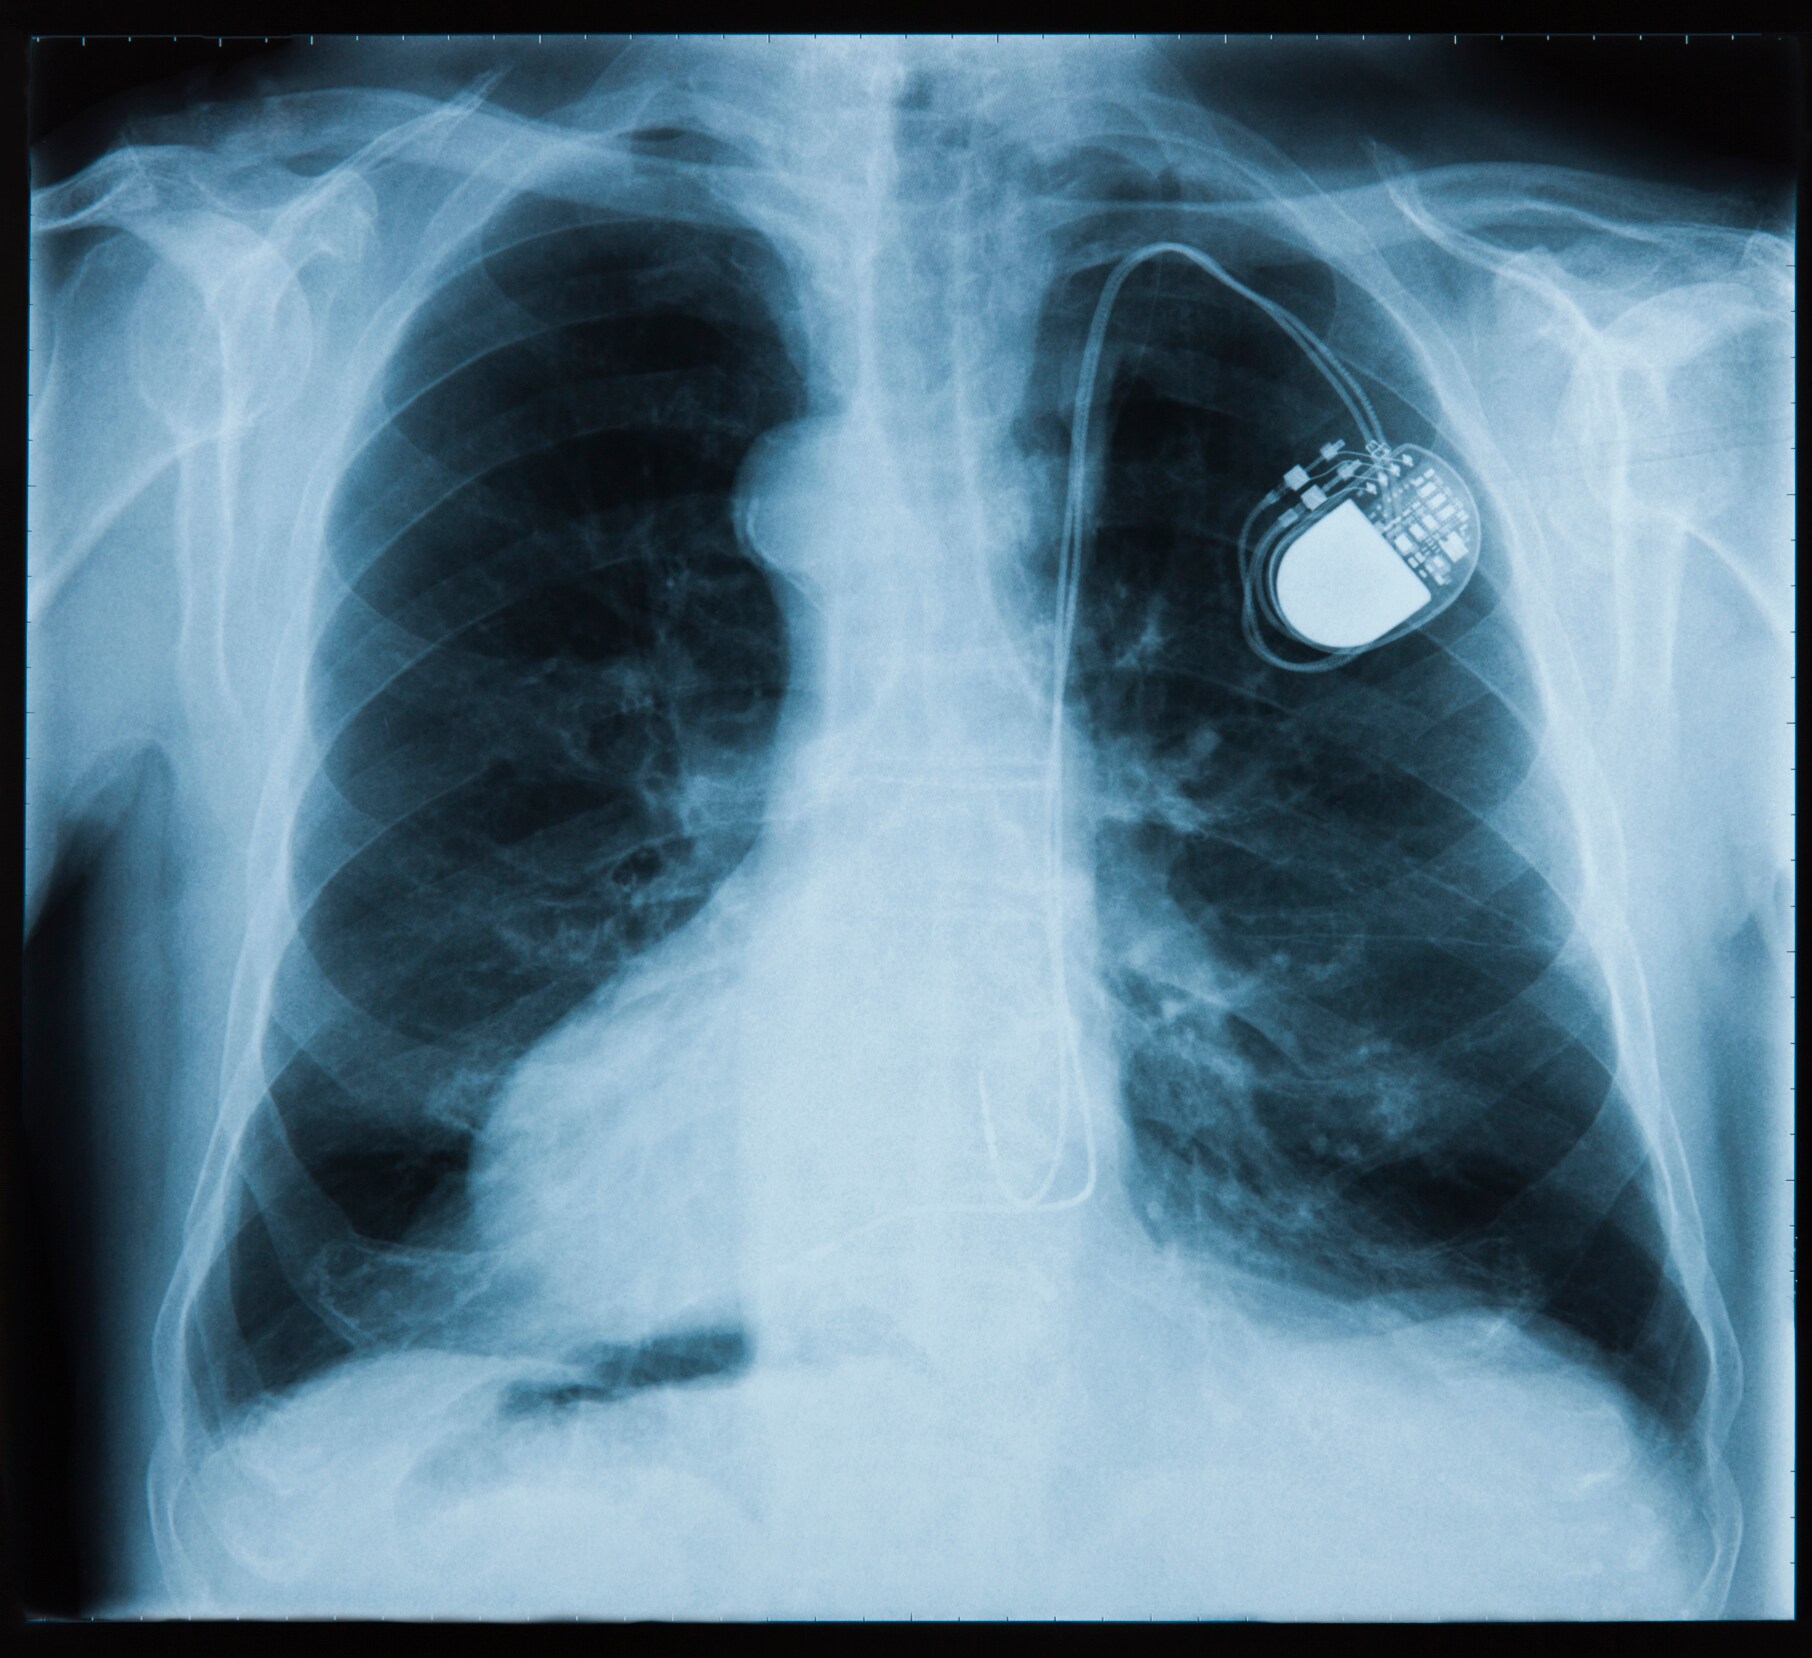

Most pacemakers contain at least two platinum-iridium electrodes.

Platinum is inert, rarely causes allergic reactions, has good electrical conductivity, and can be fabricated into tiny components, all qualities that make it an ideal material for pacemakers, stents, implantable defibrillators, and catheters. Most pacemakers contain at least two platinum-iridium electrodes. Platinum marker bands and guide wires are commonly used to place stents, and now even the stents themselves may be made with platinum alloys. Platinum marker bands are also placed on catheters and guide wires to help surgeons with device placement. Platinum-iridium electrodes are used in neuromodulators such as aural and retinal implants as well as devices used to treat Parkinson’s disease and chronic pain.